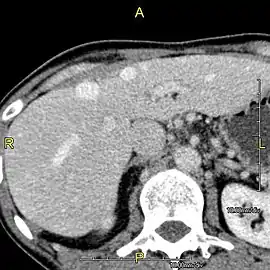

A CT scan in which the liver and portal vein are shown